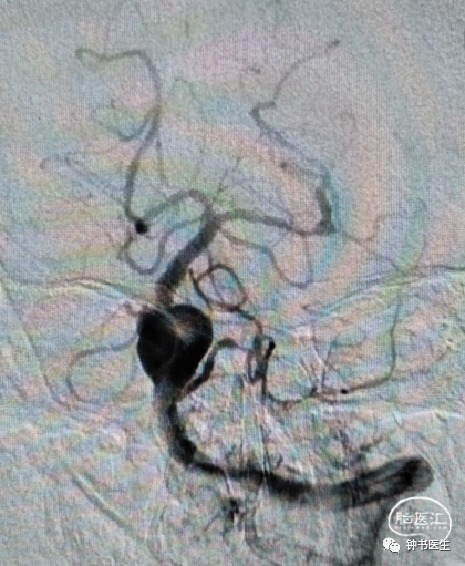

椎基底夹层动脉瘤:65Y M,脑干梗塞

术后患者无明显不适(TB 6.0X45)